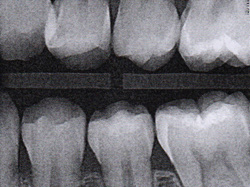

Fig 16. A 15-year-old girl with retained mandibular primary second molar and congenital absence of second premolar (Fig 16). In bitewing film small radiolucencies revealed beginning caries lesions at contact points of primary second molar and adjacent first molar (Fig 17); 12 months later, after initial SDF and 6-month follow-up SDF applications (Fig 18), radiolucencies were not evident.

Fig 17. A 15-year-old girl with retained mandibular primary second molar and congenital absence of second premolar (Fig 16). In bitewing film small radiolucencies revealed beginning caries lesions at contact points of primary second molar and adjacent first molar (Fig 17); 12 months later, after initial SDF and 6-month follow-up SDF applications (Fig 18), radiolucencies were not evident.

Figure 17

Fig 18. A 15-year-old girl with retained mandibular primary second molar and congenital absence of second premolar (Fig 16). In bitewing film small radiolucencies revealed beginning caries lesions at contact points of primary second molar and adjacent first molar (Fig 17); 12 months later, after initial SDF and 6-month follow-up SDF applications (Fig 18), radiolucencies were not evident.

Figure 18

The senior author's (TPC) private practice experience with soft-tip insertion of SDF into contacting proximal surfaces of teeth is that most beginning proximal surface caries lesions cease to progress, as evidenced by subsequent bitewing radiographic comparisons (Figure 3 through Figure 6, Figure 12 through Figure 18). The chances for success vary, however, depending on frequency of application, subsequent flossing by patients or adults flossing younger children, diet control, individual mouth chemistries, and use of fluorides for the topical effect. It must also be emphasized that office staff should make extensive efforts to inform children and parents that subsequent daily flossing is needed to accompany SDF treatments; otherwise, SDF applications will only delay the inevitable progression of caries. Flossing methods should be demonstrated for patients and for parents so they may see how to floss younger children. Showing them enlarged graphic photographs of flossing results may be helpful in this regard. Parents and patients should be made aware that if interproximal dental plaque accumulations persist without daily interruption by flossing, the acid insult will eventually take its toll on the proximal surfaces and caries lesions will progress to the point where restorative intervention may be required.